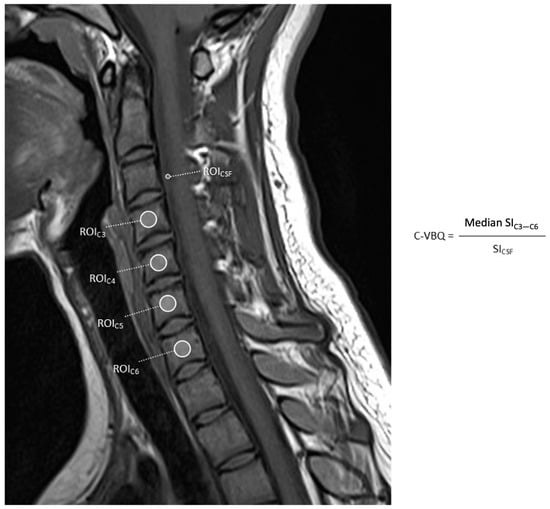

3.1. Vertebral Bone Quality Calculation

9. Cervical VBQ Scores